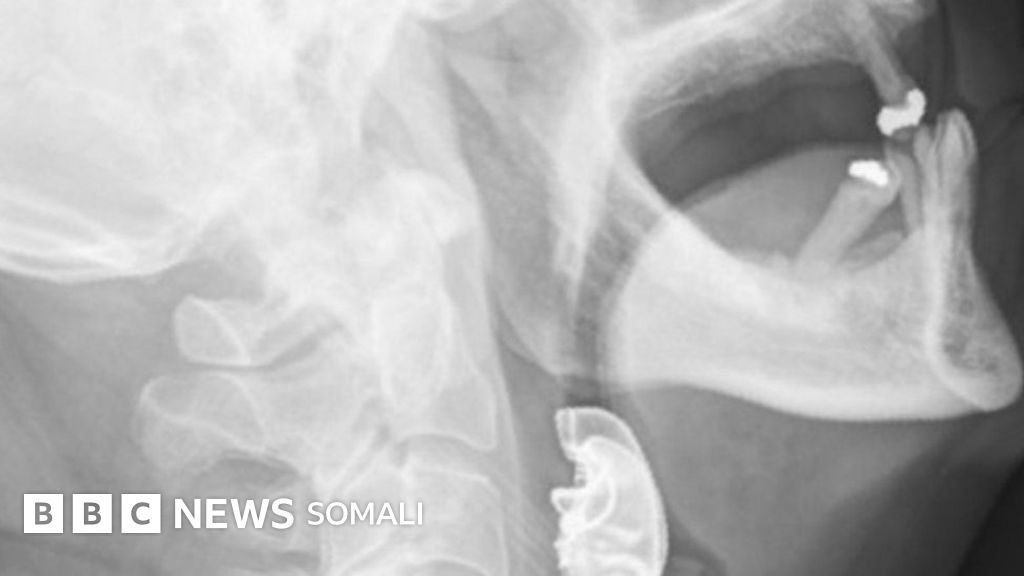

Bukaan laga qalay caloosha ayaa la sheegay in dhuuntiisa ay ku dheceen ilko macmal ah, taasi oo in la ogaado ay qaadatay muddo 8 maalmood.

Ka dib markii uu ninkan isbitaalka ku laabtay, muddo laba maalmood, dhakhaatiirta waxa ay eegeen dhuuntiisa, waxayna ku arkeen ilko macmal ah oo ku taagan.